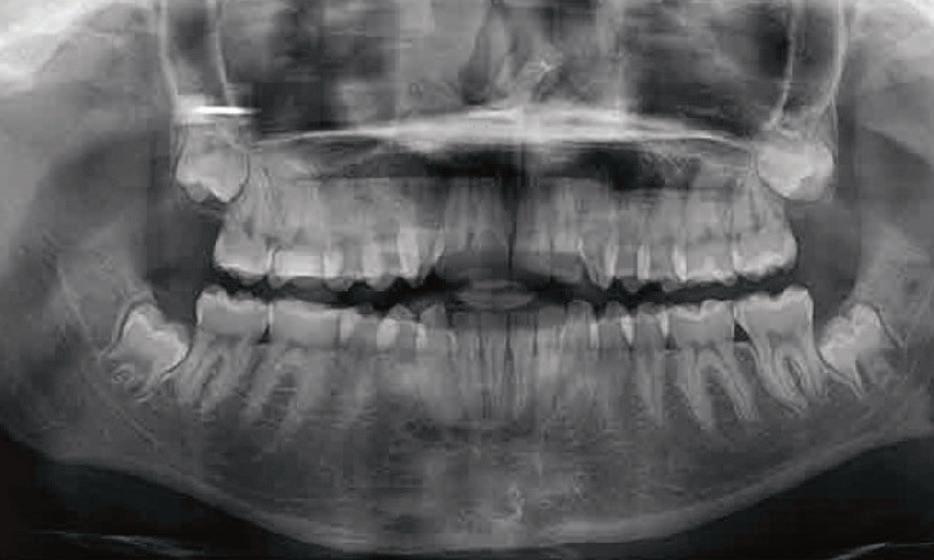

Wisdom tooth extraction is typically performed by an oral surgeon or a dentist with specialized training. Prior to the surgery, a thorough examination, including dental X-rays, is conducted to determine the tooth’s position and plan the extraction.

Understanding wisdom teeth and the potential need for their removal is essential for all patients, including youth and parents. If you or your child experiences pain, swelling or other complications related to wisdom teeth, consulting with a dental professional is crucial. With proper care and guidance, the process of wisdom tooth extraction can be managed smoothly, leading to a healthier and happier smile.